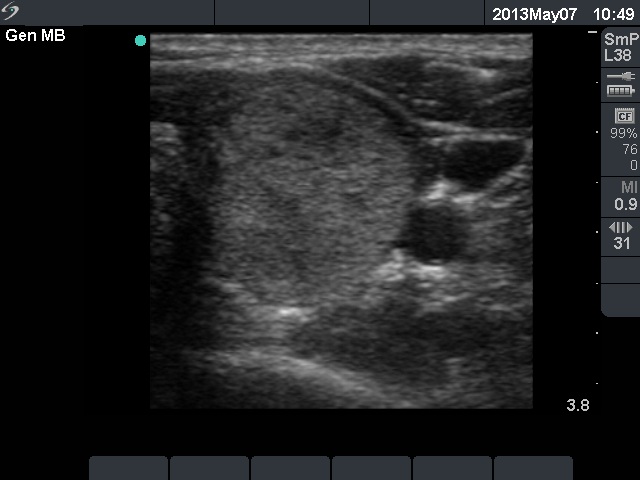

Ethanol sclerotherapy: non-toxic solid nodules - Case 5

Ten years after the therapy (ultrasonographic picture 4)

Left lobe, horizontal scan. The nodule is still significantly smaller compared with the pretreatment size.